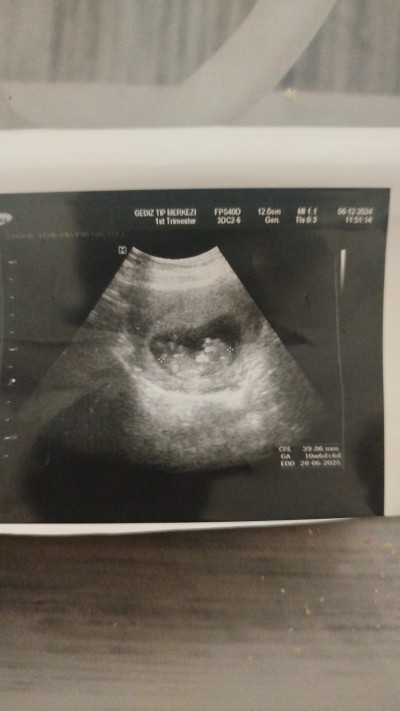

Acaba rica etsem cinsiyet tahminin de bulunabilir mısıniz

Gebelik haftası 10+4